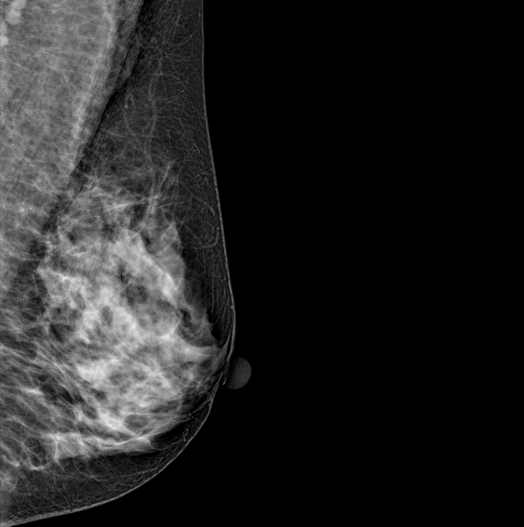

DBT (Digital Breast Tomosynthesis)

The X-ray tube moves on the breast and takes high-definition, high-resolution images with high contrast from various angles.

The images are reconstructed in 3D TO Provide accurate information about the location and condition of the lesion